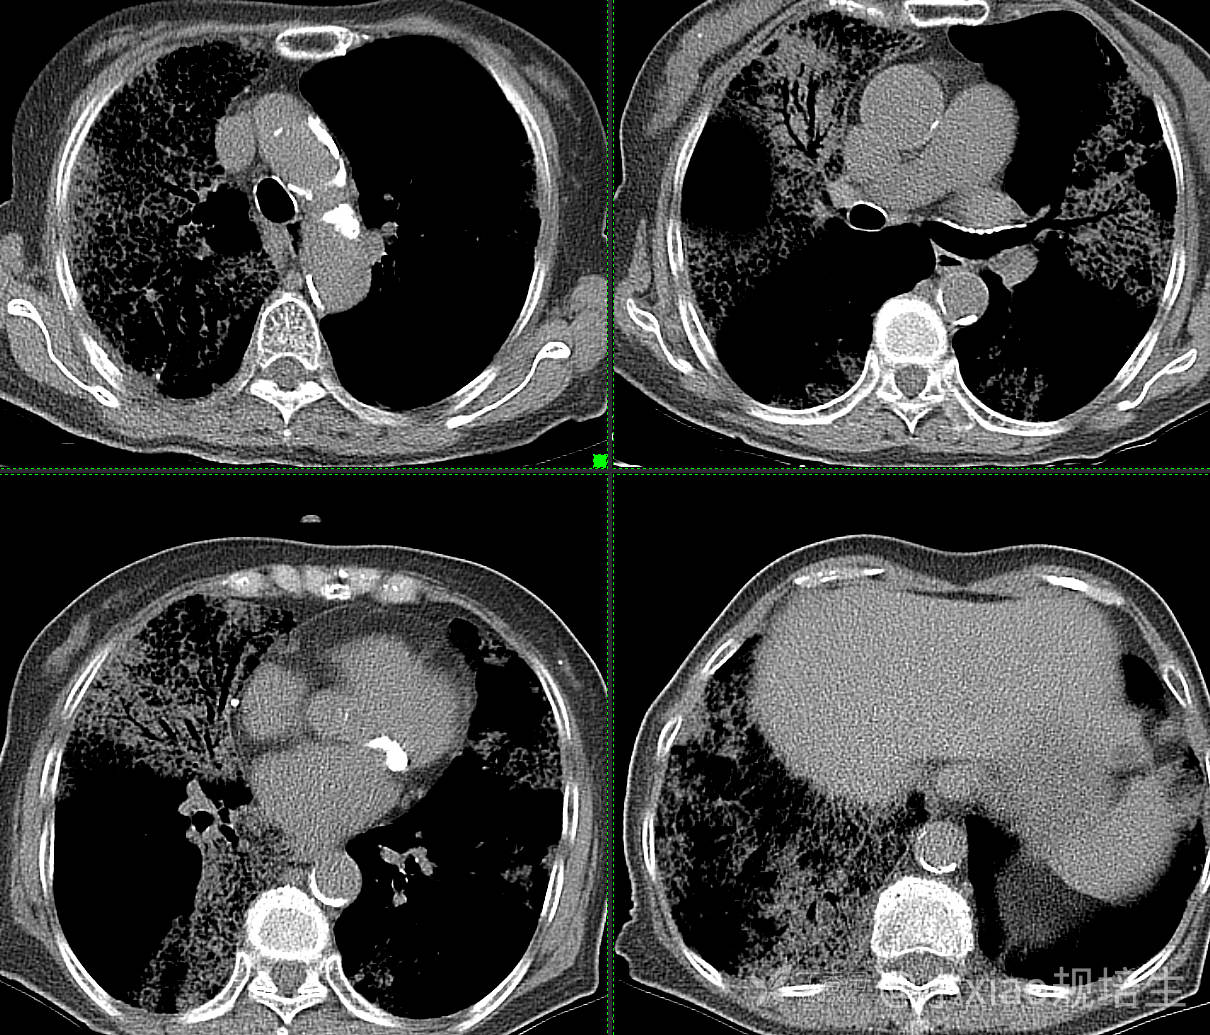

患者,女,89岁

咳嗽,咳痰一月余

肺泡蛋白沉着病 (19)

腺癌 (183)

弥漫性囊性肺病 (9)